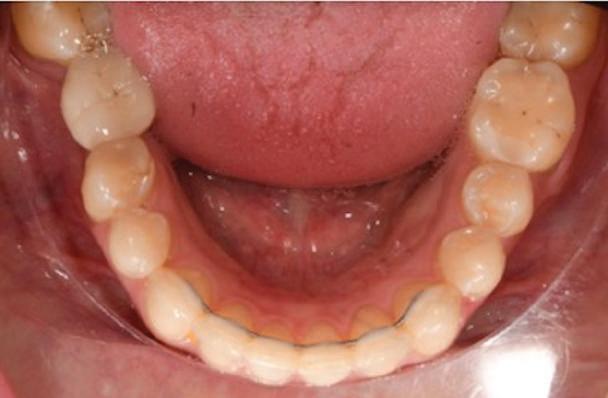

Dental Tribune Bulgarian Edition / октомври 2022 г.16 клиничен случай с алайнери Г орният латерален ре зец е вторият найчесто вродено липсващ зъб.1,2 Поради разполо жението му във видимата зона на усмивката лечение то на подобни случаи нала га мултидисциплинарен под ход, целящ отличен функцио нален и естетичен резултат. Налице са няколко лечебни мо далности, свързани с различ но разпределение на място то: първият вариант е орто донтско отваряне на място и възстановяване на липсва щия зъб с конструкция, под държана от съседните зъби3 или от имплант4, докато при втория подход разстоянията се затварят и премоларът заема мястото на канина.5 Изборът на лечебен подход трябва да бъде направен съв местно от зъболекар и паци ент въз основа на очакванията на последния и предвиди мостта на лечението. Множе ство фактори влияят върху това решение, като напри мер типа малоклузия, размера, формата и цвета на кучеш ките зъби6, оклузалните вза имоотношения (овърджет и овърбайт), лицевия профил, дължината на зъбната дъга и несъответствията в разме ра на зъбите.7 В настоящата публикация се разглежда случаят на жена в зряла възраст с вродена лип са на горен ляв латерален резец. Бяха приложени про зрачни алайнери за отваряне на място за единичен им плант и бяха постигна ти функционална оклузия и отлична естетика. ПРЕДСТАВЯНЕ НА СЛУЧАЯ Диагноза Пациентката бе на 32 годи ни, когато лечението започна, и първоначалното ѝ състоя ние бе следното (фиг. 1–3): липсващ горен ляв латерален резец; клас II, подклас I малоклузия; отклонение на горната сре динна линия вляво; Доклад на клиничен случай ЛЕЧЕНИЕ С АЛАЙНЕРИ НА ПАЦИЕНТ С АГЕНЕЗИЯ НА ЛАТЕРАЛЕН РЕЗЕЦ Д-р Iro Eleftheriadi и д-р Christodoulos Laspos, Гърция и Кипър Фиг. 1a–h Предоперативни лицеви и интраорални снимки. Фиг. 2a–e Дигитални модели преди началото на лечението. Фиг. 3 Панорамна снимка преди лечението. Фиг. 1a Фиг. 1d Фиг. 1f Фиг. 2a Фиг. 2d Фиг. 2b Фиг. 2e Фиг. 3 Фиг. 2c Фиг. 1b Фиг. 1e Фиг. 1g Фиг. 1h Фиг. 1c

Dental Tribune Bulgarian Edition / октомври 2022 г. 17клиничен случай с алайнери леко струпване в долната че люст; несъответствие по Болтън (мандибуларен излишък от 3.06 мм във фронталната зона и общо 1.47 мм); издължено лице с лицева аси метрия; конвексен профил с ретруди рана долна челюст и проми нентен нос. На мястото на зъб #46 бе на лице имплант, а зъби #16 и 26 са ендодонтски лекувани. Тези зъби бяха асимптоматич ни, затова бе взето решение да се прави релечение само при нужда. Мъдреците липсваха. Анализът на телерентгеногра фията (фиг. 4) показа ретрог натна мандибула (SNB: 74.2°) и нормална инклинация на резците както в

Цели на лечението и лечебен план Целите на лечението бяха следните: нивелиране и подреждане на зъбите и в двете зъбни дъги; отваряне на пространство за липсващия латерален резец; коригиране на отношенията при канините и моларите до клас I; и корекция на отклонението на срединната линия. Лечебният план включваше: корекция на отношенията при кучешките зъби и мола рите до клас I с дистализира не на максилата; отваряне на пространство в областта на #22 за поставя не на единичен имплант; корекция на срединната ли ния; и създаване на място за раз ширяване на зъб #12 и апрок симална редукция в долната челюст с цел подобряване на несъответствието по Болтън и осигуряване на подобра оклузия. Изпълнение на лечебния план Този случай бе изпълнен със системата за алайнери Invisalign (Align Technology). Одобреният първоначален лечебен план предвиждаше 49 алайне ра с дистализиране на задни те горни зъби до клас I (прибли зително с около 3.5 мм; фиг. 5). За бъдещия имплант в областта на липсващия латерал бе планирано пространство от 6.5 мм, докато във фронталния сегмент на долната челюст бе предвидена апроксимална редук ция. В дясната страна бутон за ластици клас II бе поставен на зъб #47 вместо на зъб #46, за да не се увреди короната на импланта. Понеже пациентката жи вееше в чужбина,

следните казуси: недобра оклу зия в дисталните зони по вре ме на дистализирането на гор ната челюст и накланяне на зъб #21 (фиг. 7). Последното се дължи на липсата на компози тен атачмънт на този зъб, каквото не бе зададено в пър Фиг. 4 Телерентгенография и цефалометричен анализ преди началото на лечението. Фиг. 5a–e Одобреният първоначален лечебен план. Фиг. 6a–h Снимки по време на лечението, показващи нуждата от внасяне на някои корекции. Фиг. 4 Фиг. 5a Фиг. 5d Фиг. 6a Фиг. 6d Фиг. 6f Фиг. 6b Фиг. 6e Фиг. 6g Фиг. 6h Фиг. 6c Фиг. 5e Фиг. 5b Фиг. 5c

планта бе поставена временна коронка (фиг. 10 и 11), докато бъде изготвена окончателна та. Бе постигнат отличен кра ен резултат. Меките тъка ни около импланта напълно заздравяха, което доприне се за перфектната хармония между бяла и розова естетика (фиг. 12–15).

Dental Tribune Bulgarian Edition / октомври 2022 г.18 воначалния план. Тези пробле ми бяха адресирани чрез допъл нителна поръчка на алайнери с торк контрол и зададено екст рудиране на задните зъби с цел установяване на добри оклузал ни контакти в дисталните об ласти, като бяха предвидени и оптимизирани атачмънти с контрол над корените за корекция на ангулацията на макси ларните резци (фиг. 8). Резултати от лечението Панорамната рентгено графия след ортодонтското лечение показа благоприятна паралелна позиция на съседни те зъби, подходяща за поставя не на имплант в областта на #22, както и конвергенция на ко рените на зъби #44 и 45 (фиг. 9), но преценихме, че няма да от деляме допълнително лечебно време за коригирането ѝ поради факта, че пациентката бе мно го доволна от постигнатия до момента резултат. След при ключване на лечението бяха постигнати отлични взаимо отношения клас I при мола рите и канините, а срединни

съвпадаха. Върху им

(LFH: 56.5 mm) и размерите на меките тъка ни останаха непроменени. На клонът на горните резци бе за пазен (Ui–FH: 115.8°), а долните резци бяха леко наклонени ве стибуларно (Li–APog: 30°; фиг. 16). ДИСКУСИЯ Липсата на зародиш на по стоянен горен латерален резец е налице при 3.5–6.5% от евро пеидната раса, като при жени е по-честа, отколкото при мъ жете в съотношение 3:2.8–10 Възможни са няколко лечебни подхода, включително замя ната му с преоформен канин, отваряне на място чрез орто донтско лечение и протетич но възстановяване, както и ав тотрансплантация. Устано вено е, че изборът за затваря не на място или за отваряне то му все още подлежи на дис кусия сред ортодонти и проте зисти.11,12 Според литературните дан ни затварянето на простран ството и замяната на липсва щия латерал с канин се предпо чита в случаи на едностранна липса на зародиш, балансиран профил, кучешки зъби и премола ри със сходна форма и цвят, дву челюстна протрузия или клас II малоклузия.13–15 Отваряне на пространство по-често се изби ра при клас I, наличие на диасте ми и треми в горната зъбна дъга или голяма разлика в размерите на канини и премолари.16 Скорошно проучване е уста новило, че изборът на лечение при конгенитално липсващ ла терал е пряко свързан със след ните фактори17: възрастта на пациента при започване на лечението; индивидуалните особености при всеки конкретен случай; и сътрудничеството между специалистите в лекуващия екип. Макар да има проучвания, фа воритизиращи леченията със затваряне на място11,18, всеки случай трябва да бъде оценяван индивидуално. В презентирания в тази статия случай бе взето решение за отваряне на мяс то и протетично възстановя ване, понеже целта бе да се по стигнат клас I отношения при канините и моларите, както и по-широка усмивка. За да се из бегнат компромиси, след лече нието бе постигнат клас I при моларите и кучешките зъби, несъответствието по Болтън бе подобрено и срединната ли ния бе коригирана. Други изслед вания демонстрират отлични естетични и функционални ре зултати при лечение с отваря не на място и протетична ре хабилитация.19 И двете лечеб ни модалности са подходящи за третиране на вродена лип са на зародиш на латерал и да ват сходни функционални и па родонтални резултати20, като при едно проучване

ти и клас II ластици е устано вено, че осигурява достатъч на дистализация без промяна на лицевата височина.23 Както се видя от цефалометричния анализ, точно това бе постиг нато и в представения случай като се има предвид, че лице вата височина остана същата като първоначалната. Предвид леката тенденция към дистал Фиг. 8a–e Поръчаните допълнителни алайнери. Фиг. 9 Панорамна рентгенография след края на лечението. Фиг. 10a–c Странични (а и с) и фронтална интраорални снимки след края на ортодонтското лечение и поставянето на импланта (b). Зъб #12 все още не беше протезиран. Фиг. 11а и b Оклузални снимки след ортодонтското лечение. Фиг. 7a Фиг. 8a Фиг. 7d Фиг. 8d Фиг. 9 Фиг. 10a Фиг. 10b Фиг. 10c Фиг. 11bФиг. 11a Фиг. 7b Фиг. 8b Фиг. 7e Фиг. 8e Фиг. 7c Фиг. 8c Фиг. 7a–e Интраоралната ситуация по време на лечението. клиничен случай с алайнери

Dental Tribune Bulgarian Edition / октомври 2022 г. 19 на отворена захапка е устано вено, че финалното адаптиране и подобряване на оклузалните контакти се установяват след повече от три месеца след лече нието.24 Следователно подобря ване на ситуацията и плътни оклузални контакти се очак ват след края на лечението. Що се отнася до избора за замест ване на липсващия латерален резец с единичен имплант и протезирането му, установе но е, че това е най-често при лаганата лечебна алтернати ва.25 Съседните зъби остават интактни и следователно най голямото предимство на този подход е съхраняването на здра ви зъбни структури. Изборът ни на лечебен план бе базиран на детайлна мул тидисциплинарна диагноза и планиране, а те категорично са ключови за постигане на оп тимални индивидуални резул тати при пациенти

но

между членовете на екипа и пациента. ЗАКЛЮЧЕНИЕ Случаите на липсващи лате рални резци трябва да бъдат третирани от перспектива та на интердисциплинарна ди агностика и лечение. Употреба та на софтуера ClinCheck има доказани предимства за плани ране, комуникация между кли ницистите и пациента и фи нализиране на лечебния план, като се адресират всички же лания и притеснения на паци ента. Настоящият доклад на клиничен случай доказва, че с помощта на съвременните ме тоди един успешен екип от спе циалисти (ортодонт, консерва тивен зъболекар и хирург) може да се стреми към отлични ре зултати и да постига есте тични и функционални усмив ки без компромиси. Ред. бел.: Статията Treatment of a patient with a congenitally missing lateral incisor using aligners: A case report е пуб ликувана за първи път в сп. aligners–international magazine of aligner orthodontics, бр. 1, издание 1/2022. Библиографията е налична при издателя. За авторите: Д-р Iro Eleftheriadi завършва дентална медицина в Атинския университет, а магистратурата си по медицинска статистика – през 2014 г. в Публичния университет в Атина, Гърция. Специализира ортодонтия и завършва през 2017 г. в Университета в Тел Авив, Израел. Предстои ѝ да защити докторан тура във Факултета по дентална медицина към Университета в Атина, Гърция. Д-р Christodoulos Laspos завършва дентална медицина през 1995 г. в Атинския университет, Гърция, а магистратурата си завършва през 1999 г. във Фа култета по дентална медицина към Университета в Тенеси, Мемфис, САЩ. Печели стипендия и специализира лечение на пациенти с лицево-челюстни малформации в Университета в Тексас, Далас, САЩ, и е сертифициран специалист от Европейския борд на ортодонтите. Той е докторант в Универ ситета в Берн, Швейцария. От 2000 г. д-р Laspos практикува в частната си ортодонтска практика в Лимасол, Кипър. Той е основател и директор на MEDICLEFT, Кипърски център за цепки и лицево-челюстни аномалии, както и директор на фондацията Synergy, която осигурява следдипломно обучение на лекари по дентална медицина. Научен съ трудник е във Факултета по дентална медицина към Европейския университет в Кипър. Д-р Laspos изнася лекции по цял свят по теми като лицево-челюстни мал формации, ортогнатна хирургия, мултидисциплинарен подход и нови технологии в ортодонтията. Той е активен член на Европейското общество на Енгел и прези дент на Европейското ортодонтско общество. Фиг. 12а–c Финални странични (а и c) и фронтална интраорални снимки (b). Фиг. 13а и b Финални оклузални снимки. Фиг. 14 Финална снимка на усмивката отблизо. Фиг. 15 Финална екстраорална снимка на усмивката. Фиг. 16 Финална телерентгенография и цефалометричен анализ. Фиг. 12a Фиг. 13a Фиг. 14 Фиг. 15 Фиг. 16 Фиг. 13b Фиг. 12b Фиг. 12c клиничен случай с алайнери